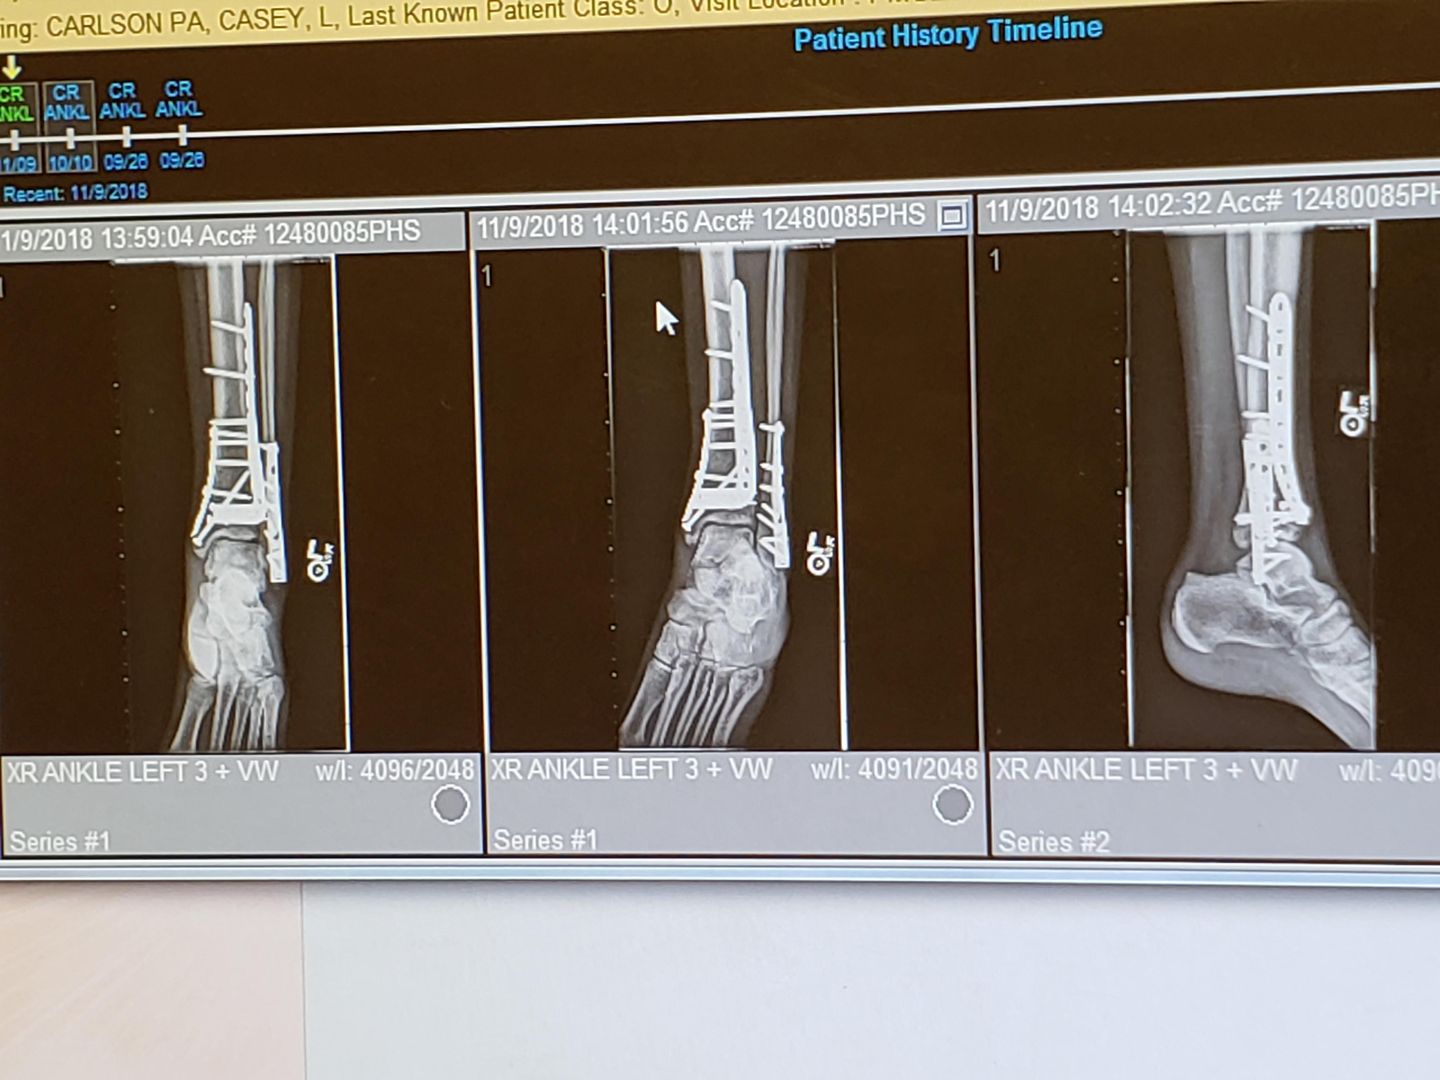

I broke my tibia and fibula down to the ankle joint (pilon fracture), 15 screws and 3 plates